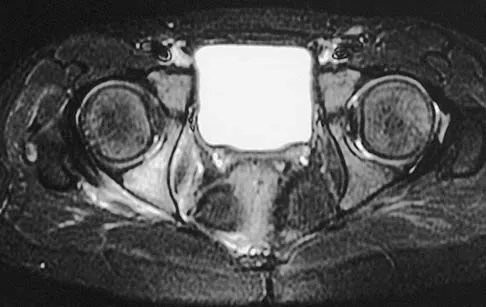

Question 32

An otherwise healthy 45-year-old woman reports the onset of severe right leg pain. Figure 20a shows an axial MRI scan of the L4-5 level, and Figure 20b shows a sagittal view with the arrow at the L4-5 level. What nerve root is the most likely source of her pain?